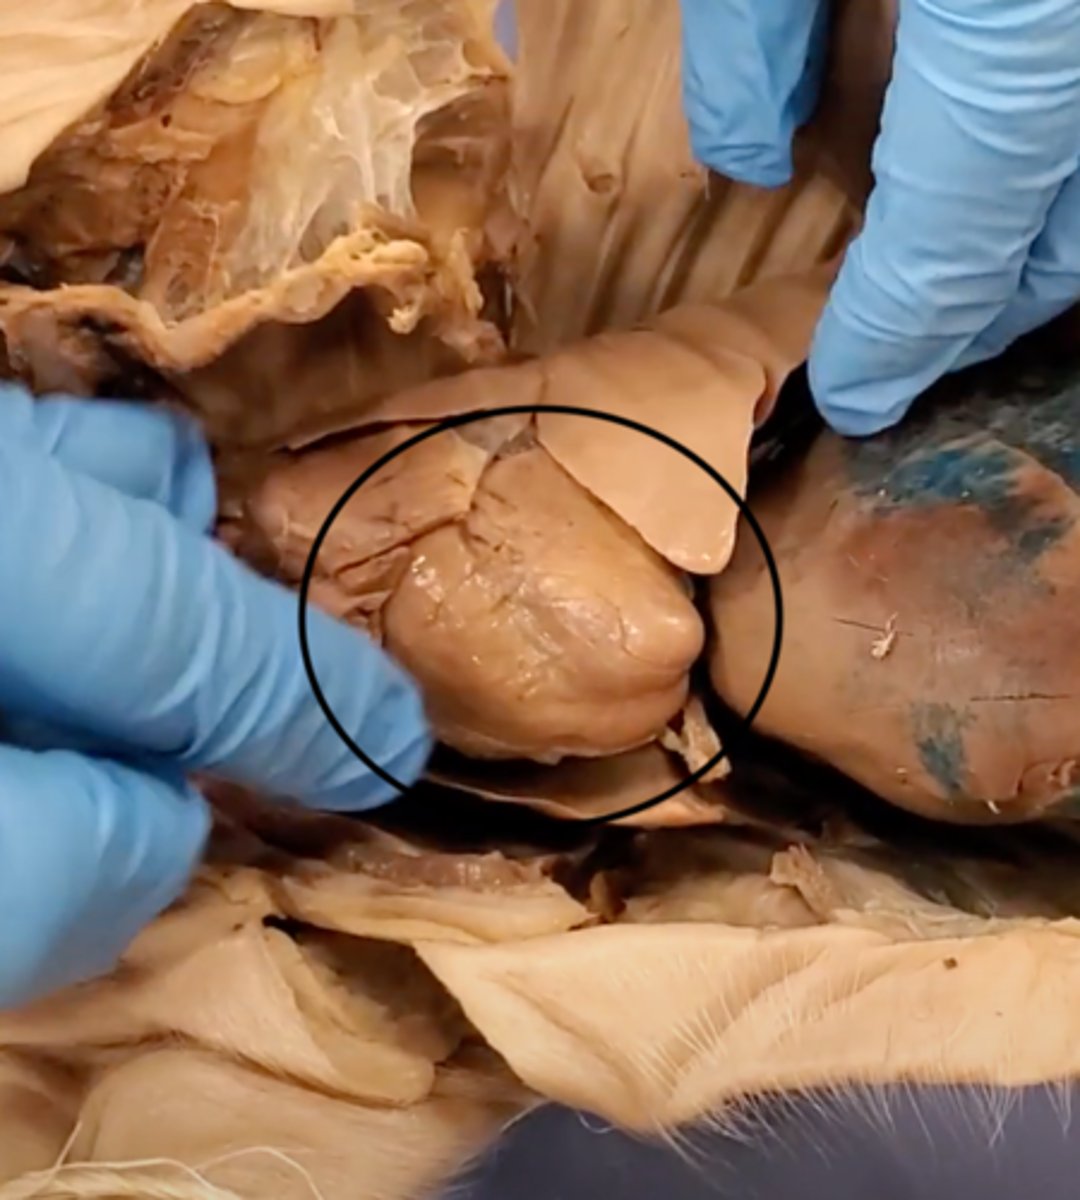

yellow sash of fat that tells you this if the front side of the heart (dissection)

pulmonary trunk (dissection)

t-shaped ribbon of fat on back side of heart (dissection)

left auricle (dissection)

right auricle (dissection)

left ventricle (dissection)

right ventricle (dissection)

right atrium (dissection)

left atrium (dissection)

bicuspid valve (dissection)

tricuspid valve (dissection)

aortic semilunar valve (dissection)

located between the left ventricle and the aorta

chordae tendineae (dissection)

thin bands of fibrous tissue that attach to the valves in the heart and prevent them from inverting

heart

A hollow, muscular organ that pumps blood throughout the body.